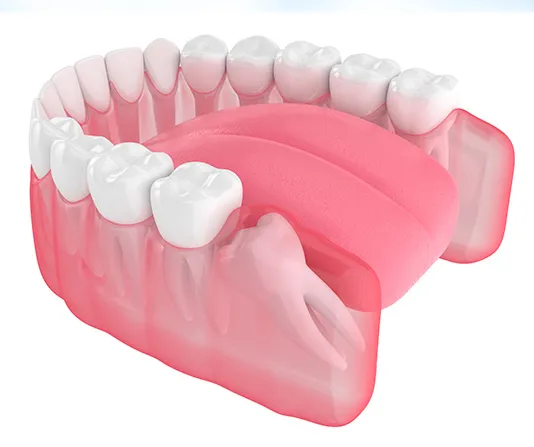

Dental implants are a long-term solution that feels and functions like a natural tooth. The implant is placed in the jawbone where it bonds with the bone, creating a secure foundation for a custom crown. Implants help maintain bone strength, improve chewing ability, and restore the appearance of your smile. With the right care, they can last for many years.